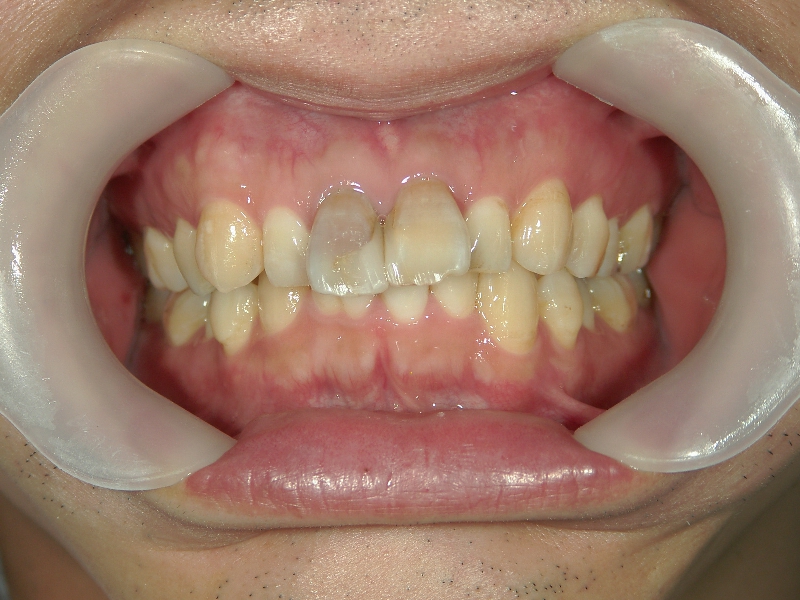

矯正歯科 治療後矯正歯科 全顎ワイヤー矯正 治療後矯正歯科(全顎ワイヤー矯正)治療後

矯正歯科 治療後 E-AMXというセラミックにて左右上1番を被せ直しました。